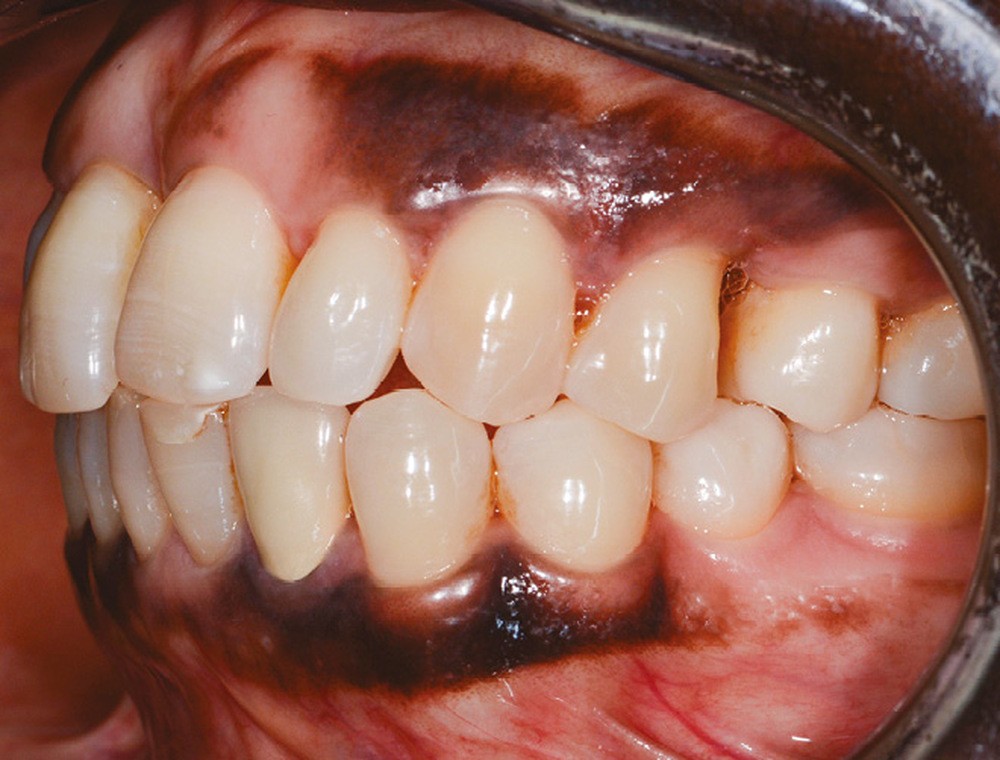

L’observation clinique après traitement parodontal initial révèle, au niveau interarcade, des rapports de classe I molaire bilatéraux associés à des rapports de bout à bout incisif. Dans la dimension verticale, elle présente une légère infraclusion antérieure. On ne note pas d’anomalie de la dimension transversale (fig. 3 à 5). À l’examen intra-arcade, on constate des diastèmes maxillaires interincisifs (1 mm), en distal de 13 (0,5 mm) et de 24 (1 mm) ainsi que des malpositions unitaires (linguoversion de 12, rotation mésio-vestibulaire disto-linguale de 24). À la mandibule, on observe une couronne céramométallique au niveau de 32 plus large de 1,5 mm que les autres incisives ainsi qu’une rotation mésio- linguale de 35 (fig. 6 à 8). En diduction, on note une interférence au niveau de 24.